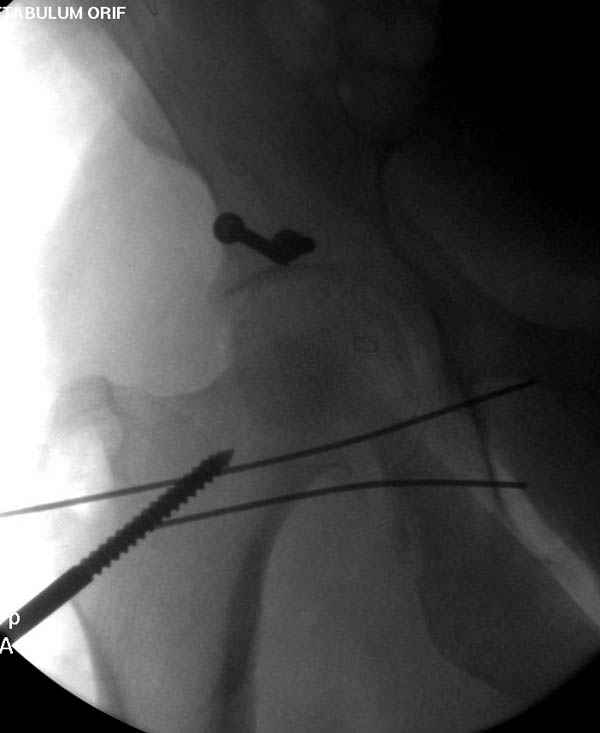

Дополнительно имеется перелом ацетабулума: задняя

колонна с полупоперечным переломом, и переломы костей лица.

На седьмой день зафиксирован перелом ацетабулума через задний доступ. Перед операцией для профилактики DVT, IVC фильтер, также получает Lovenox.

Извиняюсь за качества снимков, обычный больной в 300 фунтов, портативным ренген аппаратом не пробить.

Латеральное положение облегчает проведение тракции через вертел, за 5 мм стержень за вертел (грузом через тракционное приспособление), на обычном рентгенопрозрачном операционном столе, а для положения на животе, наверное, Judet Table более приемлем, потому что там имеется латеральное тракционное устроиство.

Там множество обычных 2.7 мм шурупов, потом идет фиксация основными пластинами.

Снимки здесь....